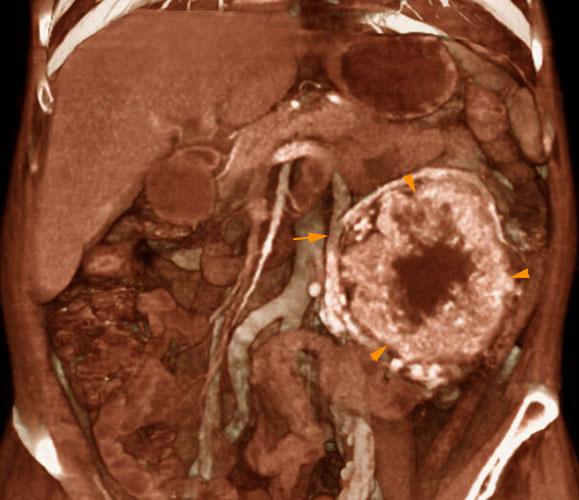

Carcinoma medular renal